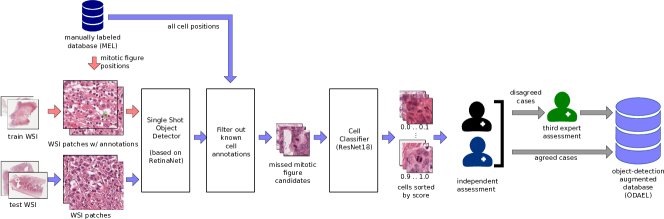

Object-Detection Augmented and Expert Labeled (ODAEL) Dataset

While one expert screened the WSIs with the help of a dedicated software solution and with great diligence, we still have to assume that, due to the partially infrequent occurrence of mitotic figures, the expert might have missed a certain percentage of mitotic figures. To take this into account, we employed a machine learning-based pipeline to find candidates for missed mitotic figures to be presented to the experts (see Figure 2). For this, we first split a preliminary dataset into three parts (each 7 WSIs), which were then subsequently each used once as a test set for a CNN-based object detector, with the WSIs of the other two parts used as training set. We used a customized version [12] of RetinaNet [16] for this purpose. All objects detected by the network were subsequently checked for existence in the MEL dataset variant. Second, we trained a cell classifier on 128 px patches cropped around the cells annotated in the currently used training part of the MEL dataset and ran the inference with all newly identified mitotic figure candidates. The cell patches were grouped into 10 groups according to their model score (where 1.0 represented cells being very likely a mitotic figure, and 0.0 very unlikely, respectively). All mitotic figures were initially shown to the first pathologist and the second pathologist independently, and in case of disagreement, the third expert rendered the final vote, like in the previous dataset variant. Through this procedure, the number of mitotic figures was increased by compared to the MEL dataset (see Table1), which is in line with previous findings [12]. The number of non-mitotic cells was increased much more significantly (). The reason for this is that all candidates that were identified by the RetinaNet (even those with low scores) were added to the list of non-mitotic figures. Comparing the individual tumor cases, we can see that the relative increase in mitotic figures is higher for the tumors with less overall mitotic figures. This highlights that missing mitotic figures is more likely for lower grade tumors due to the rareness of the event.